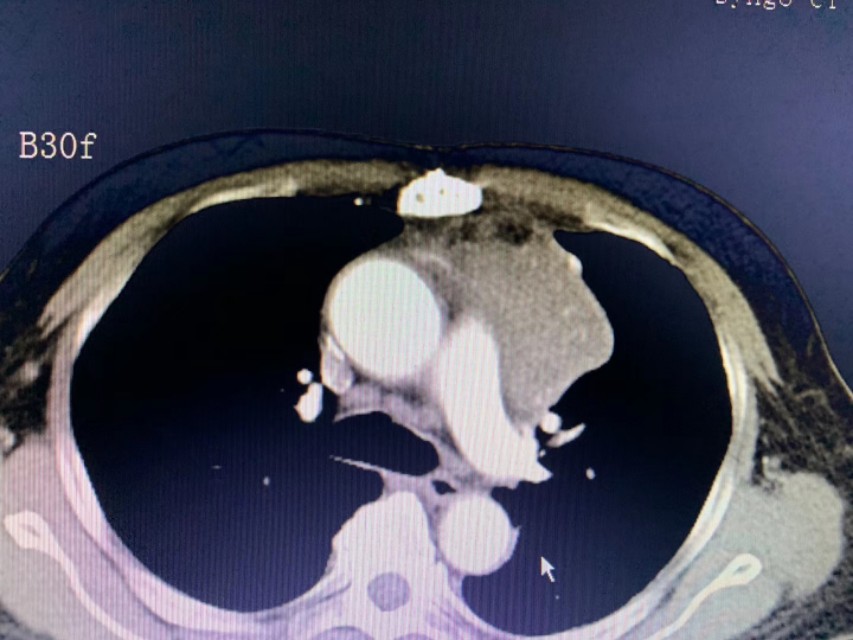

一位来自印尼患者,冠脉搭桥手术后患胸腺癌不适宜再手术,半年前已在我院行冷冻消融治疗,效果非常好。这次复查还有少许肿瘤残留,再次行冷冻消融治疗。

对不适宜手术的胸腺肿瘤,冷冻消融是一个非常好的选择。目前国际上发表的相关临床论文有四篇,分别是美国(25例)、日本(个案)、中国台湾(个案)、及中国!至今我院已经完成50多例的胸腺肿瘤冷冻消融,是国际上经验最多的医院之一。